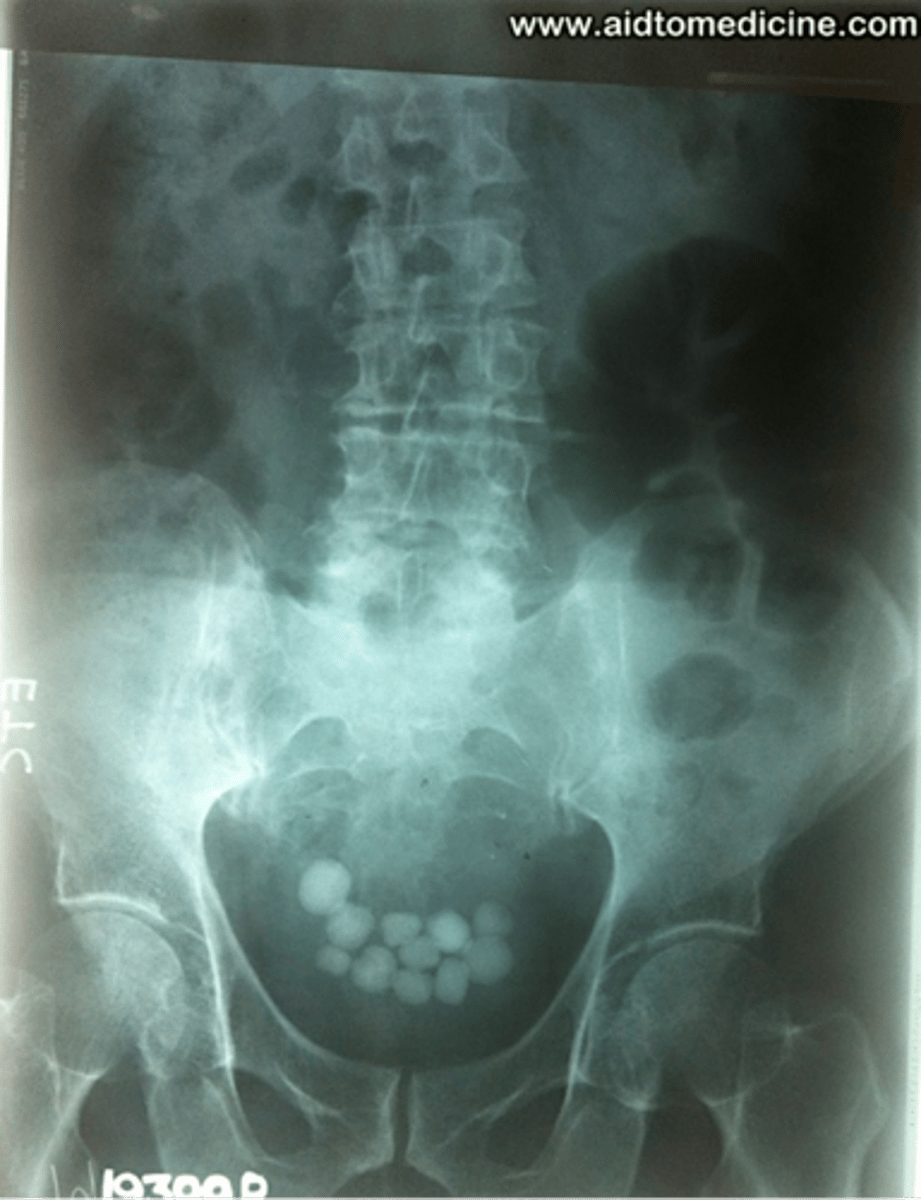

Bladder stone